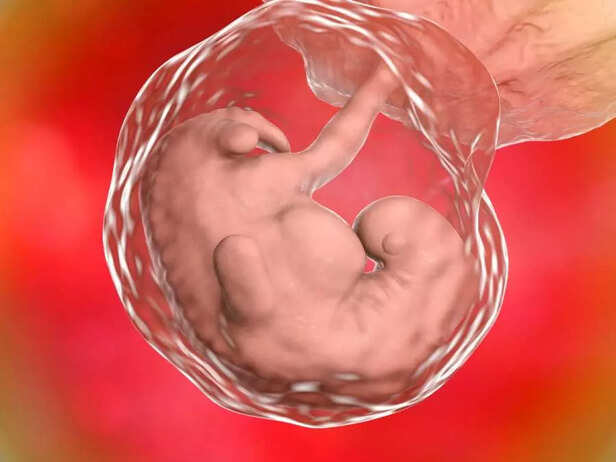

![BABY ORGAN FORMATION]()

3. Limb Formation Begins

In week 6, the foundation for your baby's limbs being is laid down, although they are still in their early stages of development:

The upper limbs, which will become the baby's arms, are beginning to grow as small, paddle-like structures coming out from the sides of the body.

Similarly, the lower limbs, which will become the baby's legs, are forming as small buds near the area where the hips will be.